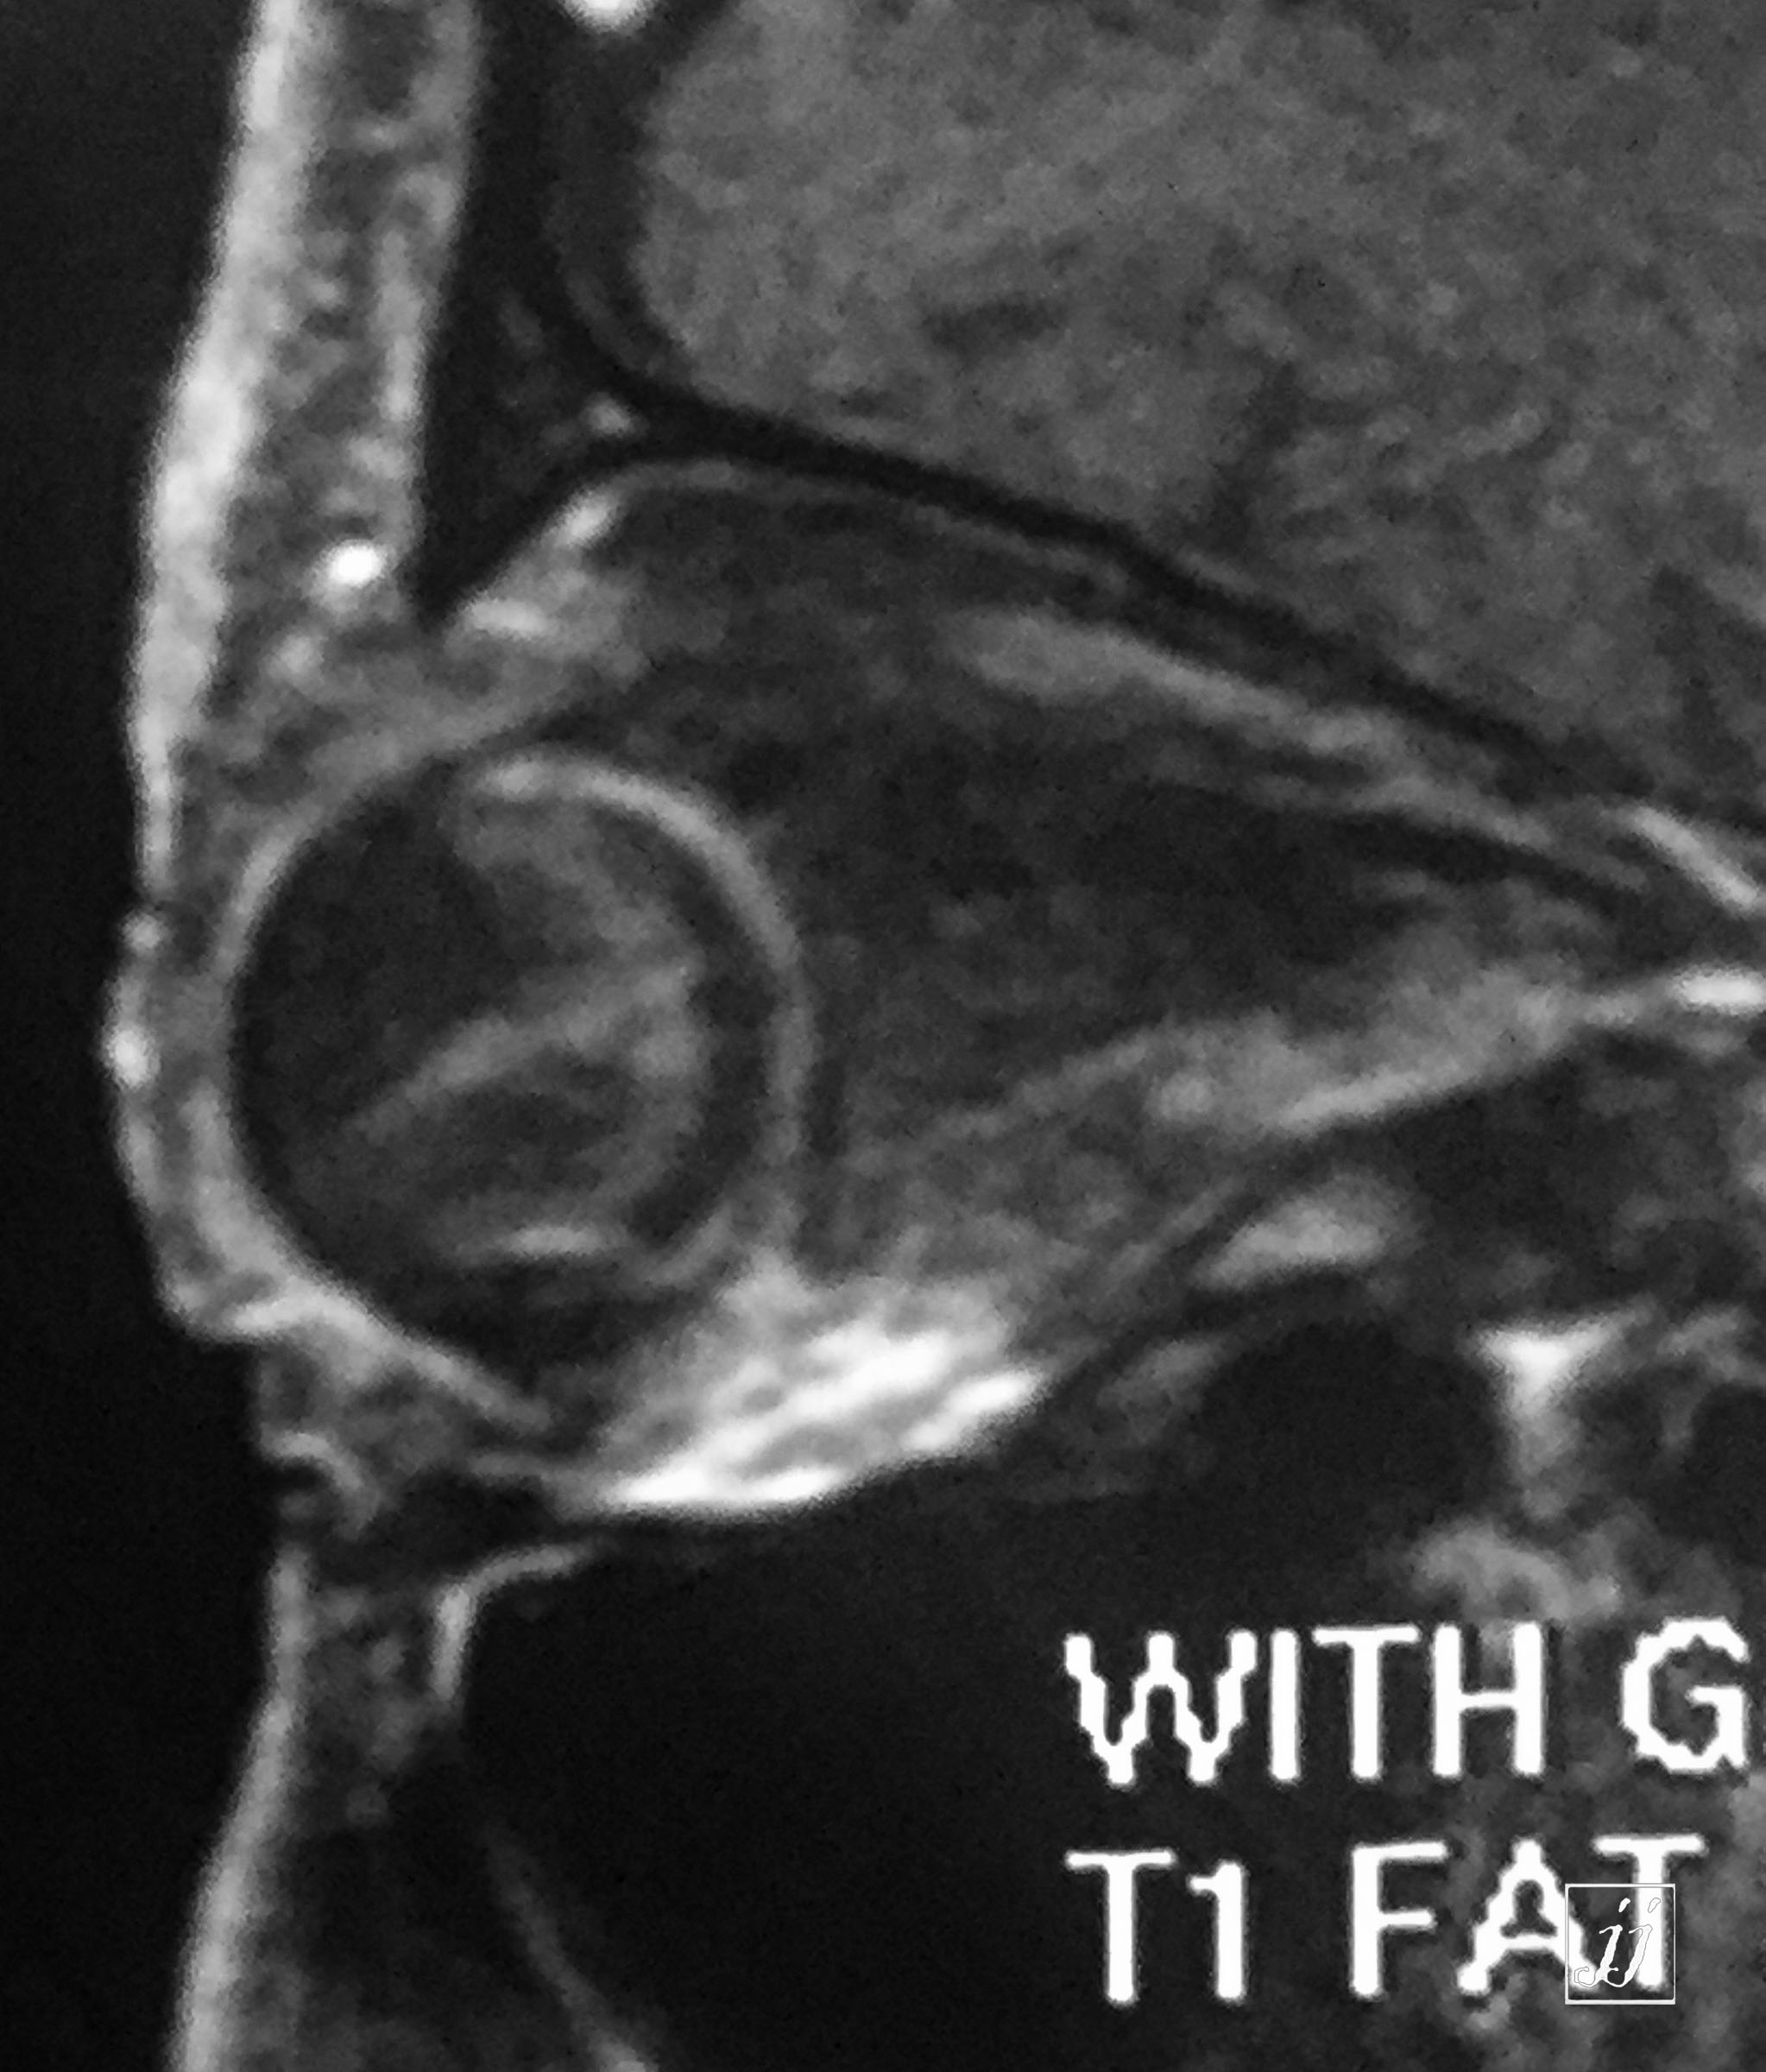

Orbit- vitreous detachment (14)